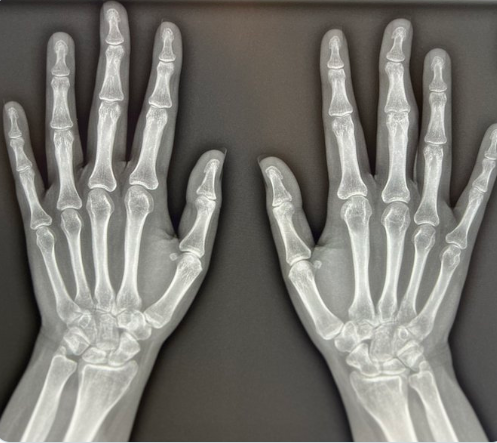

较小物体:对于如四肢的小关节(如手指、脚趾关节)等较小的被摄物体,通常可以采用相对较短的摄影距离,一般在 75-90 厘米左右。这样可以保证影像清晰度,减少 X 线的散射,提高影像质量,能清晰显示小关节的骨质结构、关节间隙等细节。